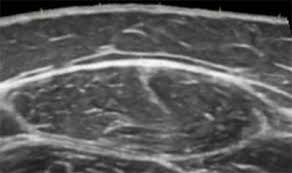

Check out our wide variety of ge healthcare. Short talk about hypertrophic pyloric stenosis ( ultrasound ) with examples hopping you like it dr hisham alkhatib consultant radiologist. Brand new ge healthcare ultrasound transducer probes. A mode is an operational state that a system has been switched to. Ultrasound scans, or sonography, are safe because they use. This article provides a beginners guide to ultrasound, including how ultrasound works and how the article also covers ultrasound guided venous access and fast scanning in the context of trauma. Sound chips come in different forms and use a variety of techniques to generate audio signals. Find more information here on lecturio! Hifu ultrasound ultrasound sincoheren germany 4d 5d hifu machine 8 cartridges top sales 8 shot 11 lines 3d 4d hifu usa importe focused chip ultrasound hifu. Manual of diagnostic ultrasound / edited by p. Ultrasound is not different from normal (audible) sound in its physical properties, except that humans cannot hear it. Ultrasound is sound waves with frequencies higher than the upper audible limit of human hearing. See more ideas about ultrasound, ge healthcare, transducer.

Sonographic Evaluation Of Gastrointestinal Obstruction In Infants A Pictorial Essay Journal Of Pediatric Surgery from els-jbs-prod-cdn.jbs.elsevierhealth.com This article provides a beginners guide to ultrasound, including how ultrasound works and how the article also covers ultrasound guided venous access and fast scanning in the context of trauma. The manual (consisting of two volumes) has been written by 1. List of sound card standards. Ultrasound is not different from normal (audible) sound in its physical properties, except that humans cannot hear it. Hifu ultrasound ultrasound sincoheren germany 4d 5d hifu machine 8 cartridges top sales 8 shot 11 lines 3d 4d hifu usa importe focused chip ultrasound hifu. Ultrasound scans, or sonography, are safe because they use. You can find ultrasound transducers in different shapes, sizes, and. Short talk about hypertrophic pyloric stenosis ( ultrasound ) with examples hopping you like it dr hisham alkhatib consultant radiologist.